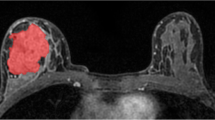

To identify the magnetic resonance imaging (MRI) features associated with epidermal growth factor (EGFR) expression level in lower grade gliomas using radiomic analysis.

270 lower grade glioma patients with known EGFR expression status were randomly assigned into training (n=200) and validation (n=70) sets, and were subjected to feature extraction. Using a logistic regression model, a signature of MRI features was identified to be predictive of the EGFR expression level in lower grade gliomas in the training set, and the accuracy of prediction was assessed in the validation set.

A signature of 41 MRI features achieved accuracies of 82.5% (area under the curve [AUC] = 0.90) in the training set and 90.0% (AUC = 0.95) in the validation set. This radiomic signature consisted of 25 first-order statistics or related wavelet features (including range, standard deviation, uniformity, variance), one shape and size-based feature (spherical disproportion), and 15 textural features or related wavelet features (including sum variance, sum entropy, run percentage).

A radiomic signature allowing for the prediction of the EGFR expression level in patients with lower grade glioma was identified, suggesting that using tumour-derived radiological features for predicting genomic information is feasible.